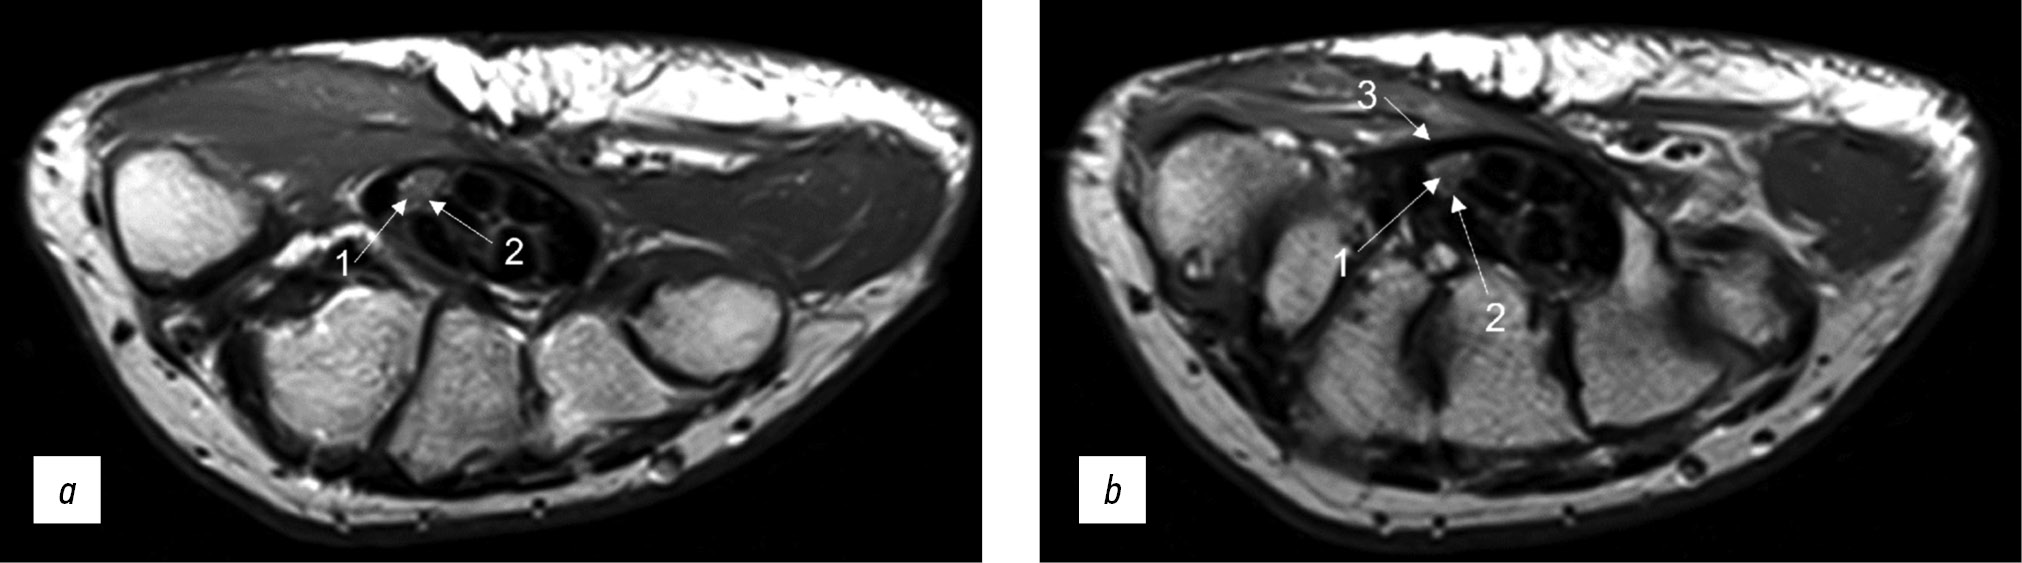

Fig. 2. Magnetic resonance imaging of the hand in T2 mode in a patient with carpal tunnel syndrome. An axial projection: (a) at the level of proximal epiphyses of metacarpal bonesand (b) at the level of distal parts of the capitate bone (1: individual fascicles as part of the median nerve, 2: epineurium, and 3: flexor retinaculum with a thickness of up to 1.29 mm).